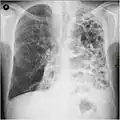

Una radiografia del torace e un esame emocromocitometrico completo possono essere utili per escludere altre condizioni patologiche presenti al momento della diagnosi.[51]

I segni caratteristici alla radiografia sono polmoni iper-espansi, diaframma appiattito, aumento dello spazio aereo retrosternale e la presenza di bolle. La presenza di tali segni può aiutare a escludere altre malattie polmonari, come la polmonite, l'edema polmonare o uno pneumotorace.[23]

Radiografia del torace che mostra una severa BPCO. Si notino le ridotte dimensioni del cuore in confronto a quelle dei polmoni.